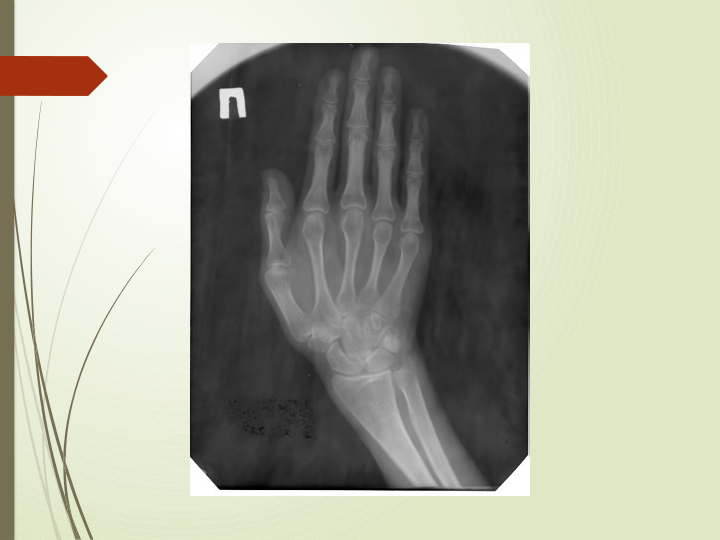

Sinishlar

 Sinish-suyakning mexanik

yaxlitligini buzilishi.

 Sinishning asosiy

belgilari:Sinish yoki yoriq

liniyasi mavjudligi.

 Suyak sinishining

yordamchi rentgenologik

belgilariga singan joy

shaklining o'zgarishi

(deformatsiya), suyak o‘qi

yo'nalishining o'zgarishi,

singan suyak bo'laklari

borligi, yumshoq

to'qimalarning shishganligi,

qattiq og'riq borligi,

harakatning cheklanishi

yoki yo'qolishi kiradi.